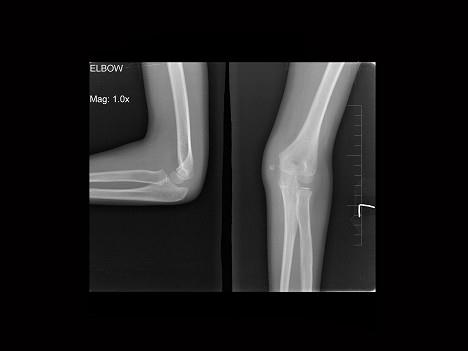

问题 男,9岁,左肘外伤,结合图像,最可能的诊断为?(?)

选项 A.左肱骨内上髁骨骺1度分离 B.左肱骨内上髁骨骺2度分离 C.左肱骨内上髁骨骺3度分离 D.左肱骨内上髁骨骺4度分离 E.左肱骨内上髁骨骺5度分离

答案 B